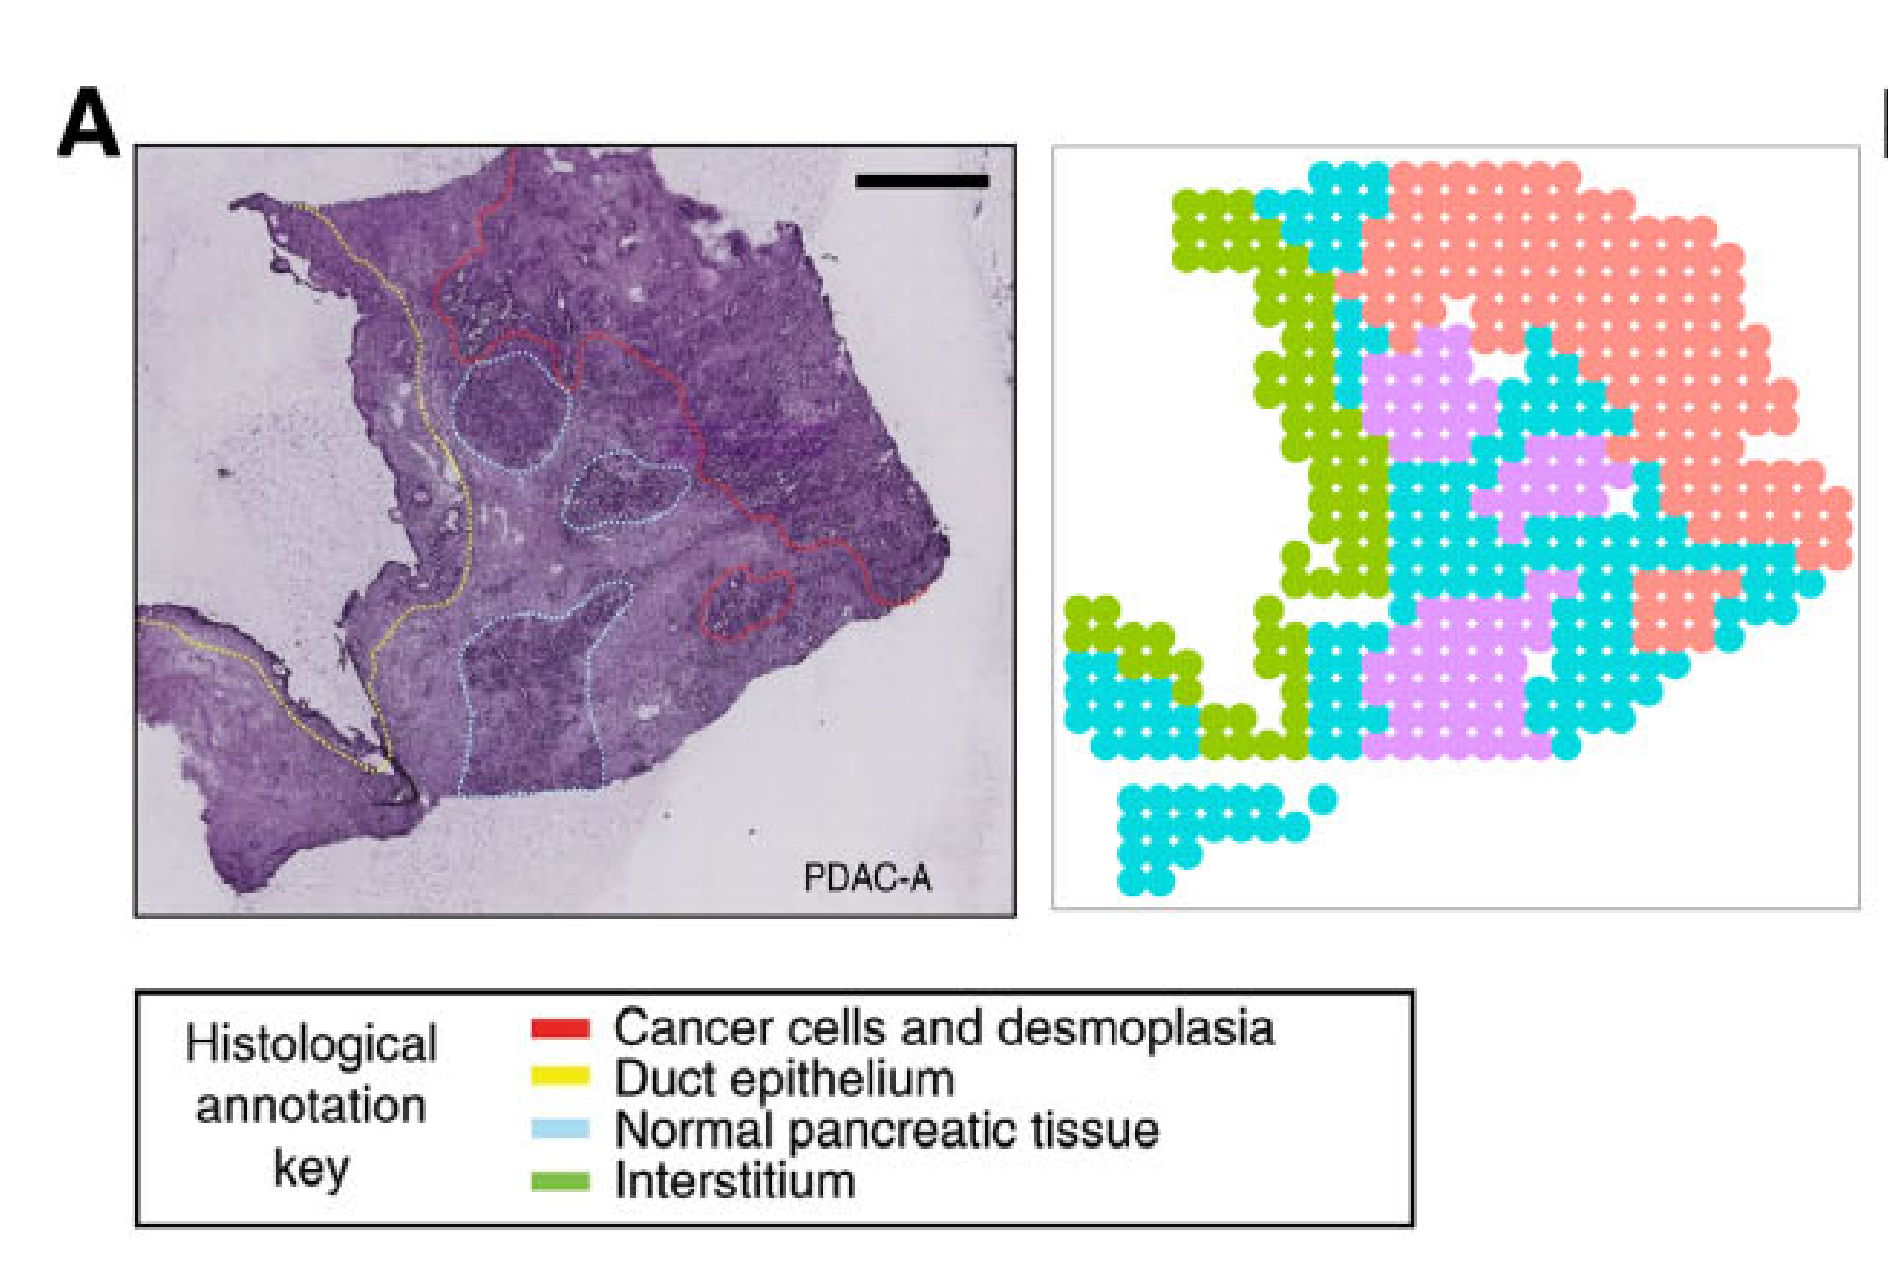

Wei R. et al. - 2022

Spatial charting of single-cell transcriptomes in tissues

Condition Dimension

N/A

Data Components

Biological Annotation

Data

Metadata

None

Modality

Sequencing-based

Resolution of observation

Functional tissue unit

Visualized Elements

Observation

Biological

Tissue

Abstraction

None

Chart Type

Histological image

Communicative/Contextualization

Annotation

Comparative Design

None

Layout

Spatial : Physical

Scalability Strategy

None (Item-level)

Where are tumor regions located within the spatial architecture of a tissue section?